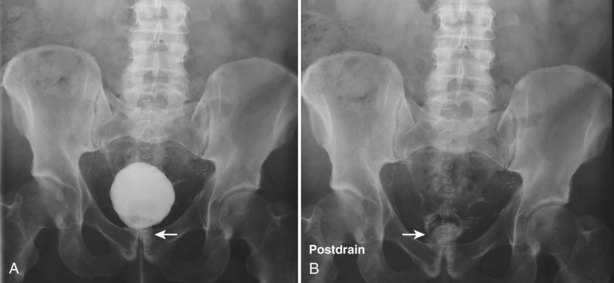

The patient is positioned supine. An abdominal plain radiograph is obtained before the introduction of contrast material (Fig. 4–8A). A commonly employed technique is to insert a small-gauge catheter into the ostomy of the loop, advancing it just proximal to the abdominal wall fascia. The balloon on such a catheter can then be inflated to 5 to 10 mL with sterile water. By gently introducing contrast through the catheter, the loop can be distended, usually producing bilateral reflux into the upper tracts. Oblique films should be obtained in order to evaluate the entire length of the loop (Fig. 4–8B). Because of the angle at which many loops are constructed, a traditional anteroposterior (AP) view will often show a foreshortened loop and could miss a substantial pathology. A drain film should be obtained (Fig. 4–8C). This may demonstrate whether there is obstruction of the conduit.

Figure 4–8 Loopography in a patient with epispadias/exstrophy and ileal conduit urinary diversion. The plain film (A) shows wide diastasis of the pubic symphysis. After contrast administration via a catheter placed in the ileal conduit, free reflux of both ureterointestinal anastomoses is demonstrated (B). A postdrain radiograph (C) demonstrates persistent dilation of the proximal loop indicating mechanical obstruction of the conduit (arrows).